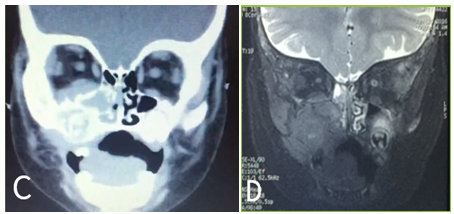

Contrast MRI: increased volume of soft structures in the right half of the face, involves soft and muscular tissues surrounding the alveolar process of the right maxilla, displaces upward orbital floor structures and moderate soft tissue reinforcement. (Figure 1B) Simple CT: soft tissue volume increase in the medial wall of the right maxillary sinus that partially obstructs the nasal cavity, remodeling and bone infiltration of the anterior wall of the maxillary sinus and occupied by density to liquid (Figure 2A) (Figure 2B).

Figure 2 (A) Single CT scan of the coronal section: observe a tumor with soft tissue density located on the anterior side of the right maxillary sinus with apparent involvement of the nasal cavity, and extension to orbit as well as bone destruction. (B) MRI increased focal volume of soft structures in the middle of the right side involving soft tissue and muscle that surrounds the maxillary sinus, lower edge of the orbit and elevates the lower rectus muscle causing mild proptosis, intermediate intensity is observed with moderate restriction to the diffusion of water, which suggests high cellularity content.